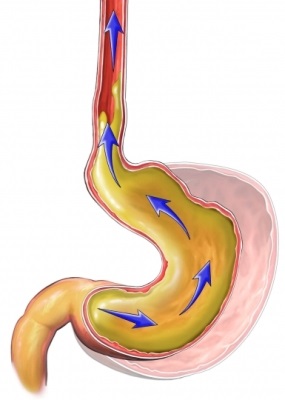

reflux gastroesofagian este un fenomen fiziologic, în primul an de viață. Diferența dintre „fiziologic“ și „patologic“ boala de reflux gastro-esofagian in copilarie si copilarie este determinată nu numai de numărul și severitatea episoadelor de reflux (evaluare folosind 24 h pH-monitorizare), dar cel mai important, prezența complicațiilor asociate cu intarziere de dezvoltare, esofagitei erozive, formarea stricturii esofagiene și boli respiratorii cronice. Alte complicatii observate la adulți cu BRGE, cum ar fi esofag și displazia mucoasei esofagiene Barrett, apar la copii mai puțin frecvent.

- Relaxărilor tranzitorii de sfincter esofagian inferior. 94% dintre episoade de reflux la copii sunt asociate cu această condiție, astfel încât acum este considerat a fi principala legătură în patogeneza bolii de reflux gastroesofagian;